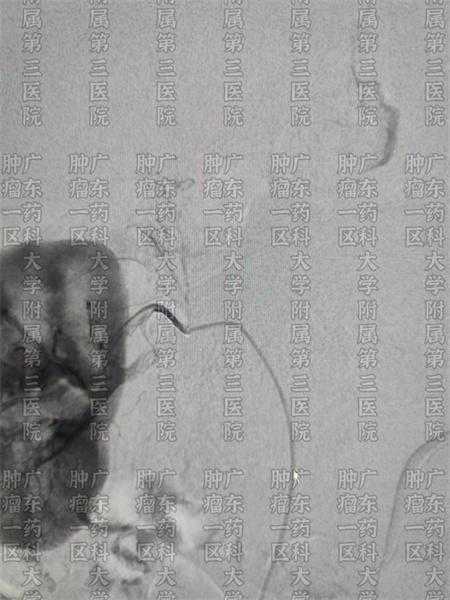

图片源于科室拍摄